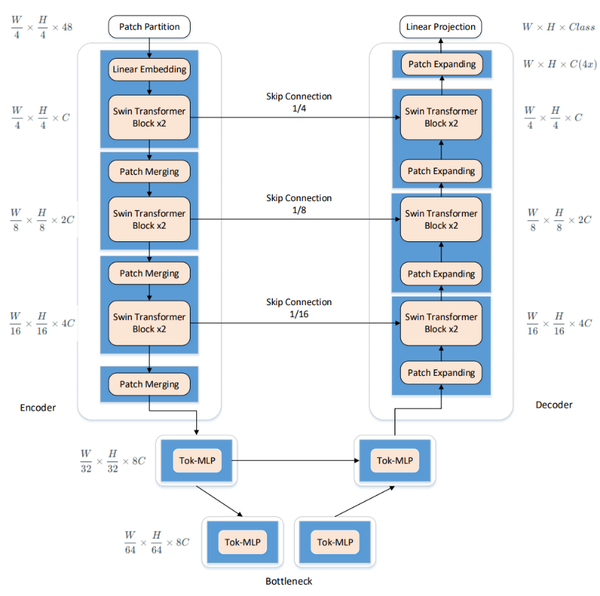

3. Improved U-Net network

The enhanced U-Net network presented in this paper intelligently integrates the traditional U-Net with elements from Swin-Unet. It utilizes the U-Net structure as the backbone, replacing its convolutional units with Swin Transformer Blocks derived from Swin-Unet. This integration allows for the effective combination of global and local contextual information, thus enhancing segmentation accuracy and robust generalization. Additionally, multi-layer perceptrons are employed at lower levels to model complex features, which significantly reduces both computational complexity and the number of parameters, while still maintaining high segmentation accuracy. The comprehensive framework of this model is showed in Figure 3.

|

| Figure 3. Schematic of the improved U-Net network structure |

3.1 Improved network composition

3.1.1 Encoder

In the encoder, traditional convolutional operations, typical in the U-Net network, are replaced with Swin Transformer Blocks from the Swin-Unet architecture to enhance feature learning. Following each operation, a patch merging layer is utilized for downsampling, reducing the size and channel count of the feature maps. Downsampling takes place at a factor of 2 during each operation, wherein elements are selected at fixed positional intervals along both row and column directions before being concatenated.

3.1.2 Shifted MLP

3.1.3 Tokenized MLP stage

3.1.4 Decoder

The decoder has a symmetric structure to the encoder, both composed of Swin Transformer block unit modules. The key distinction involves the use of patch expansion operations in the decoder, which essentially serve as the inverse of patch merging operations. This reversal process is critical for reconstructing the image from compressed features to its original dimensionality during the decoding phase. It performs upsampling operations on the features extracted by the decoder and reassembles the feature maps into higher-resolution ones.

3.1.5 Skip connection

Similar to most U-shaped network structures, skip connection operations fuse the feature information of downsampling and upsampling, effectively reducing information loss during downsampling to achieve better thyroid nodule segmentation.